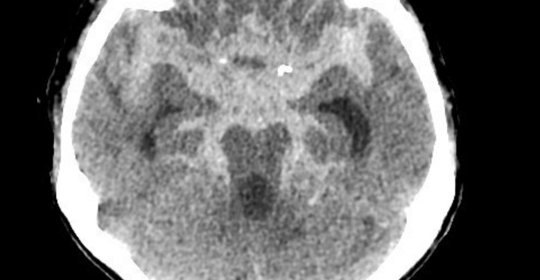

小腦中風:恢復情況、治療及危險期

小腦中風:前兆、原因及治療方法

急性腦梗塞:飲食調理與注意事項

急性腦梗塞:診斷與治療